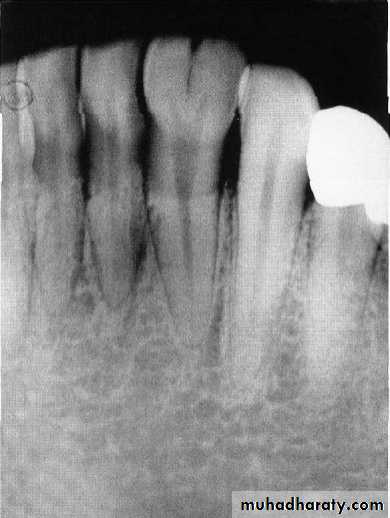

Roots of the primary molars being more delicate and divergent(flare) as they approach the apex , this to accommodate the succedaneous bicuspid , this point is very important when you extract the primary molars with unresorbed roots(care should be taken to the permanent successor).

Pulp pathosis of the primary molars in the form of lamina dura breakdown occurs in the furcation areas while in the permanent teeth occurs at the apical area(apex).

Flared roots of the molars- use caution as premolar buds are located betweenthe roots